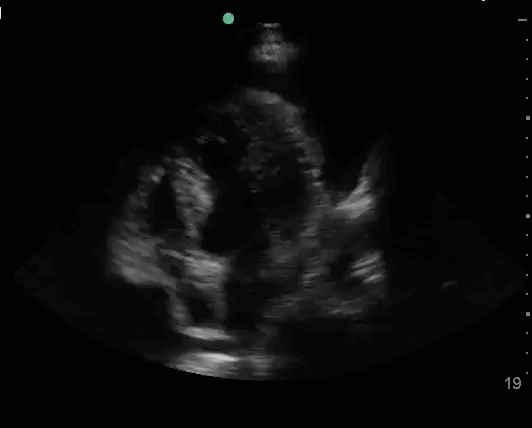

Another COVID-19 issue is the high rates of venous thromboembolism (VTE) in patients with severe disease. Cui et al reported a 25% incidence of VTE in 81 ICU patients with COVID-19.9 Klok et al described their experience in the Netherlands with 184 ICU patients with COVID-19, and they identified a 27% incidence of VTE. A majority of these cases were pulmonary embolisms (PEs).10

Although echocardiography is poorly sensitive for PE, it has reasonably high specificity. Echocardiographic signs of PE reflect right heart strain and dysfunction.

Keep in mind that some patients develop right heart dysfunction and pulmonary hypertension due to COVID-19, acute respiratory distress syndrome (ARDS), and mechanical ventilation, even in the absence of PE. Echocardiographic findings of right heart dysfunction should be interpreted in the context of the clinical scenario and other investigations like the d-dimer or assessment of the leg veins for deep vein thrombosis.

Newer evidence shows that echocardiographic signs of right heart dysfunction are associated with mortality. Li et al assessed 120 consecutive patients with COVID-19 and found that more advanced RV measurements like RV longitudinal strain, RV fractional area change, and tricuspid annular plane systolic excursion (TAPSE) were independent predictors of higher mortality.11 Argulian et al reported a 31% incidence of RV dilation in 105 patients with COVID-19. Mortality was 41% in patients with RV dilation compared to 11% in patients without RV dilation. On their analysis, RV enlargement was the only variable significantly associated with mortality.12